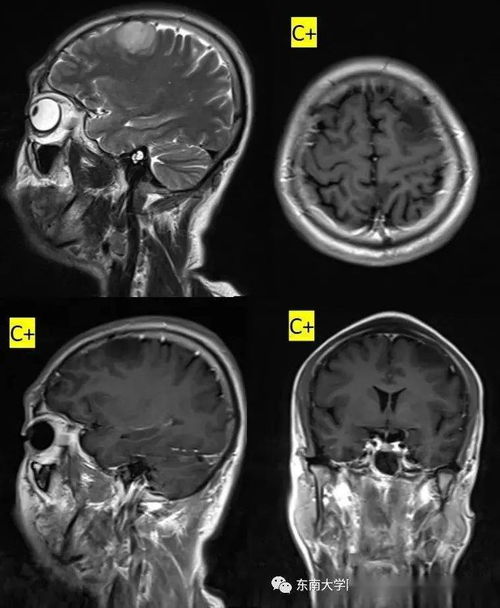

手术治疗适用于某些神经系统疾病,如脑肿瘤、脑出血等。